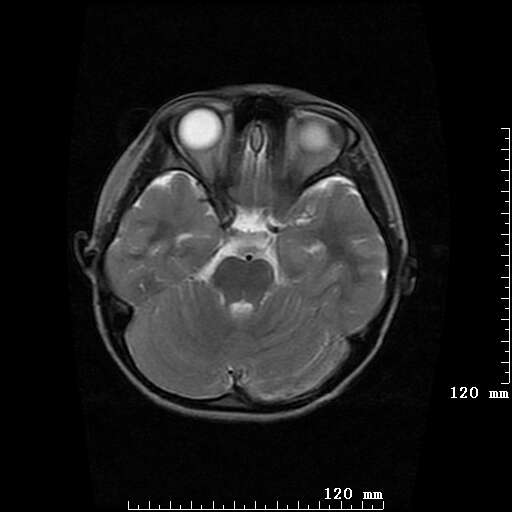

女,7岁,三岁才说话、走路。现智力尚可,走路不稳。临床怀疑大脑发育不全。

考虑 脑白质发育不良

脑折质变薄,双侧侧脑室稍扩张,支持考虑脑折质发育不良

侧脑室周围白质软化症。

考虑胼胝体发育不全,髓鞘形成不良。

支持考虑胼胝体发育不全,髓鞘形成不良。

脑裂畸形伴灰质异位

侧脑室周围白质数量减少,侧脑室不对称性扩大,左侧侧脑室后角呈方形改变,脑沟加深,结合临床考虑脑室周围白质软化症(pvl)。期待结果!

只看出灰质异位

支持脑白质发育不良。